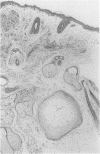

AIMS: To assess the incidence of foreign body giant cell reactions and ossification in benign/melanocytic naevi; and to examine their pathological features to gain an insight into their pathogenesis. METHODS: Intradermal (n = 185) and compound naevi (n = 110) from a routine histology service, together with 60 naevi submitted to an ophthalmic pathologist, were examined for foreign body reactions and ossification. Additional cases were identified prospectively in the course of routine reporting. The clinical and pathological features of positive cases were assessed. RESULTS: Foreign body reactions were identified in nine (4.9%) intradermal and four (3.6%) compound naevi, but in none of the naevi from around the eye. One intradermal naevus showed ossification. A further 11 naevi showing foreign body reaction and five showing ossification alone were identified prospectively. The 24 naevi showing a foreign body reaction had a similar age and sex distribution to controls but were more likely to occur on the head and neck. The reaction usually occurred deep to the naevus, sometimes in relation to a hair follicle, and fragments of hair or keratin were identified in most. Osteoid or bone was present within the reaction in five. In six other naevi, all from the head and neck of women, osteoid or mature bone was present deep to the naevus in the absence of a giant cell reaction. CONCLUSIONS: Foreign body giant cell reactions occur not uncommonly in relation to benign naevi, as a result of follicular damage, possibly due to trauma. The similar siting of foci of bone suggests that ossification occurs as a secondary phenomenon in these cases.